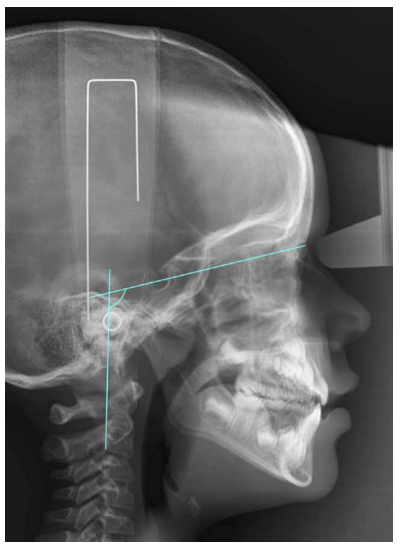

La postura cráneo-cervical se llevó a cabo a través de las variables OPT-SN, que se refiere ángulo formado por SN y la línea que discurre a través del punto más póstero-superior y más póstero-inferior del odontoides (Figura 1).